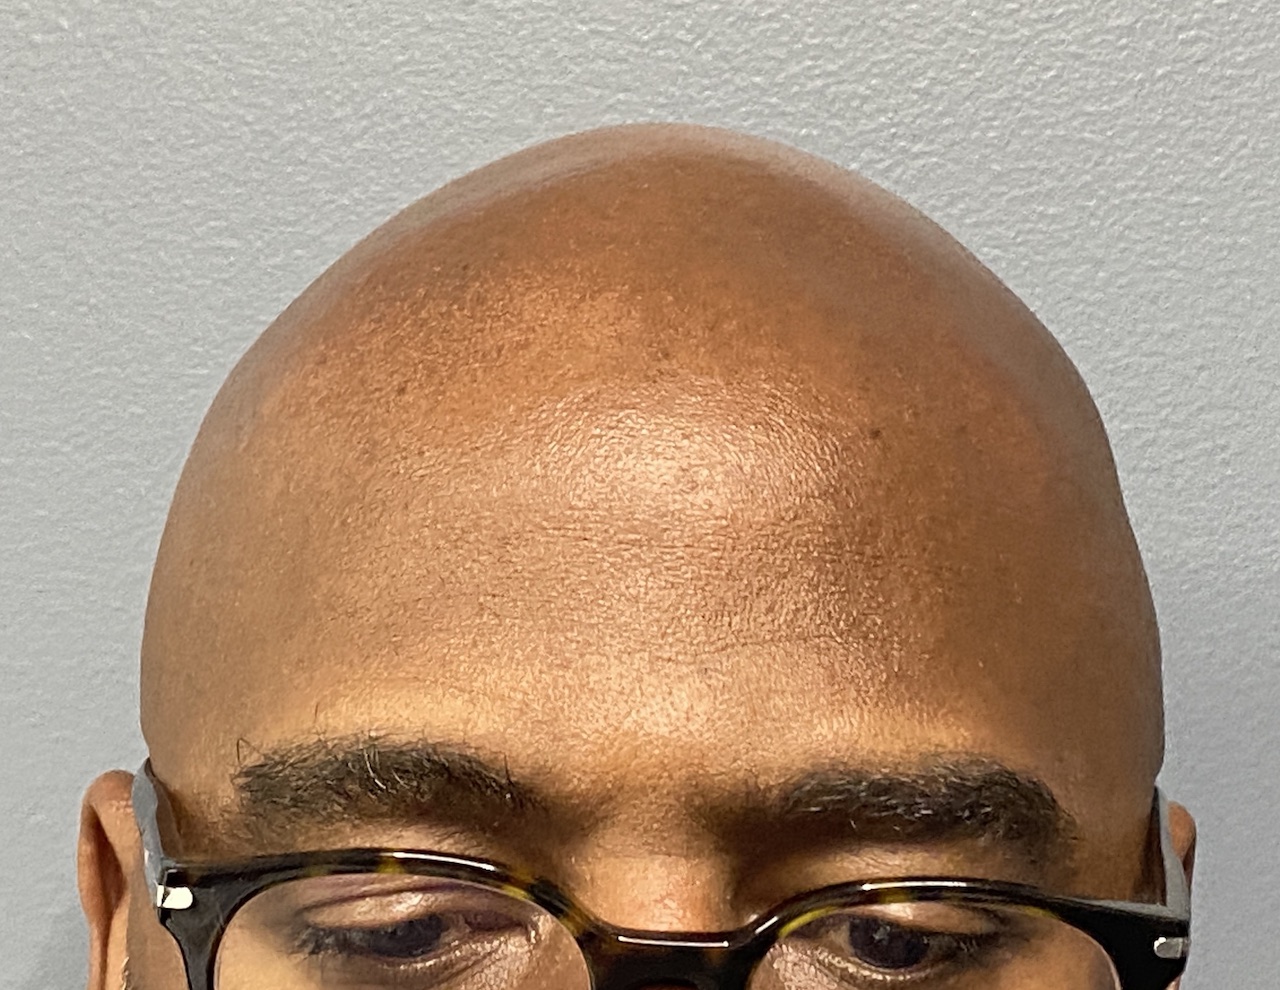

Patient 100

Desire for reshaping of an asymmetric flat back of the head in a shaved head male.

A combined back of the head reshaping procedure was done with a custom skull implant, sagittal ridge reduction and a right temporal muscle reduction.

Desire for reshaping of an asymmetric flat back of the head in a shaved head male.

A combined back of the head reshaping procedure was done with a custom skull implant, sagittal ridge reduction and a right temporal muscle reduction.